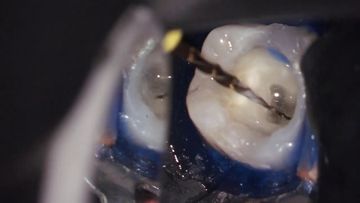

/education-service/media/default/68500/2777e2ef.jpg)

20min

Lesson

Broken file retreival from a lower molar

Radu Brata

Clinical Video